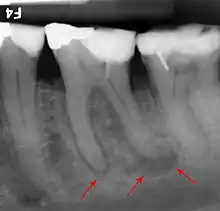

- Radiographs utilized to find dental caries and bone loss laterally or at the apex.

Decay (green) with apical abscess (blue)

Gutta-percha point indicating abscess origin